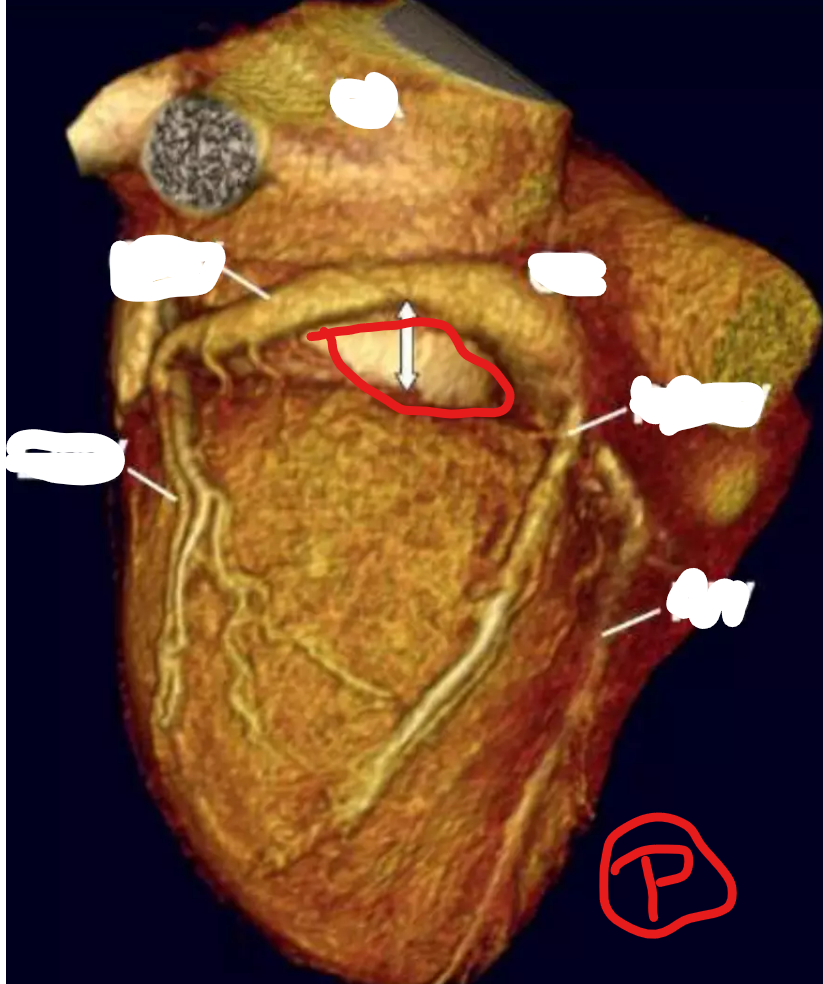

Q

Left Circumflex Branch

RCA

Left Coronary Artery/ Left Main

Right Coronary Artery